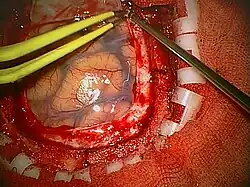

Craniotomia é uma operação cirúrgica em que um retalho ósseo é temporariamente removido do crânio para acessar o cérebro. Craniotomia é uma operação crítica realizada em pacientes que sofrem de lesões cerebrais ou traumatismo cranioencefálico Craniotomia se distingue da craniectomia (em que o retalho ósseo do crânio não é reposto imediatamente, permitindo o cérebro inchar, reduzindo assim a pressão intracraniana) e de trepanação, a criação de um orifício através do crânio para acessar a dura-máter. O tamanho e localização das craniotomias variam de acordo com o objetivo e estrutura a ser abordada. As craniotomias de pacientes vítimas de traumas crânio-encefálico, por exemplo,variam com o tamanho do hematoma a ser drenado e a necessidade de descompressão do tecido cerebral - variam de trepanações únicas para hematomas localizados até as ditas craniotomias descompressivas para tumefações cerebrais difusas.Atualmente, vêm sendo empregadas craniotomias pequenas para algumas lesões profundas (como tumores) e cirurgias de aneurisma cerebral ("Key-hole surgery").Normalmente as pessoas que se submetem a algum tipo de cirurgia invasiva cerebral, por se tratar de uma região com muita vascularização e comprometimento terciário, acaba tendo sequelas, sejam elas de primeira ou segunda ordem.

A craniotomia é realizada a partir da abertura do crânio onde permite o acesso às estruturas abaixo do crânio onde é permitido realizar a retirada de um tumor cerebral ou um coagulo sanguíneo o que resulta na recuperação do tecido cerebral ou de vasos sanguíneos e interrupção de um sangramento intracraniano.